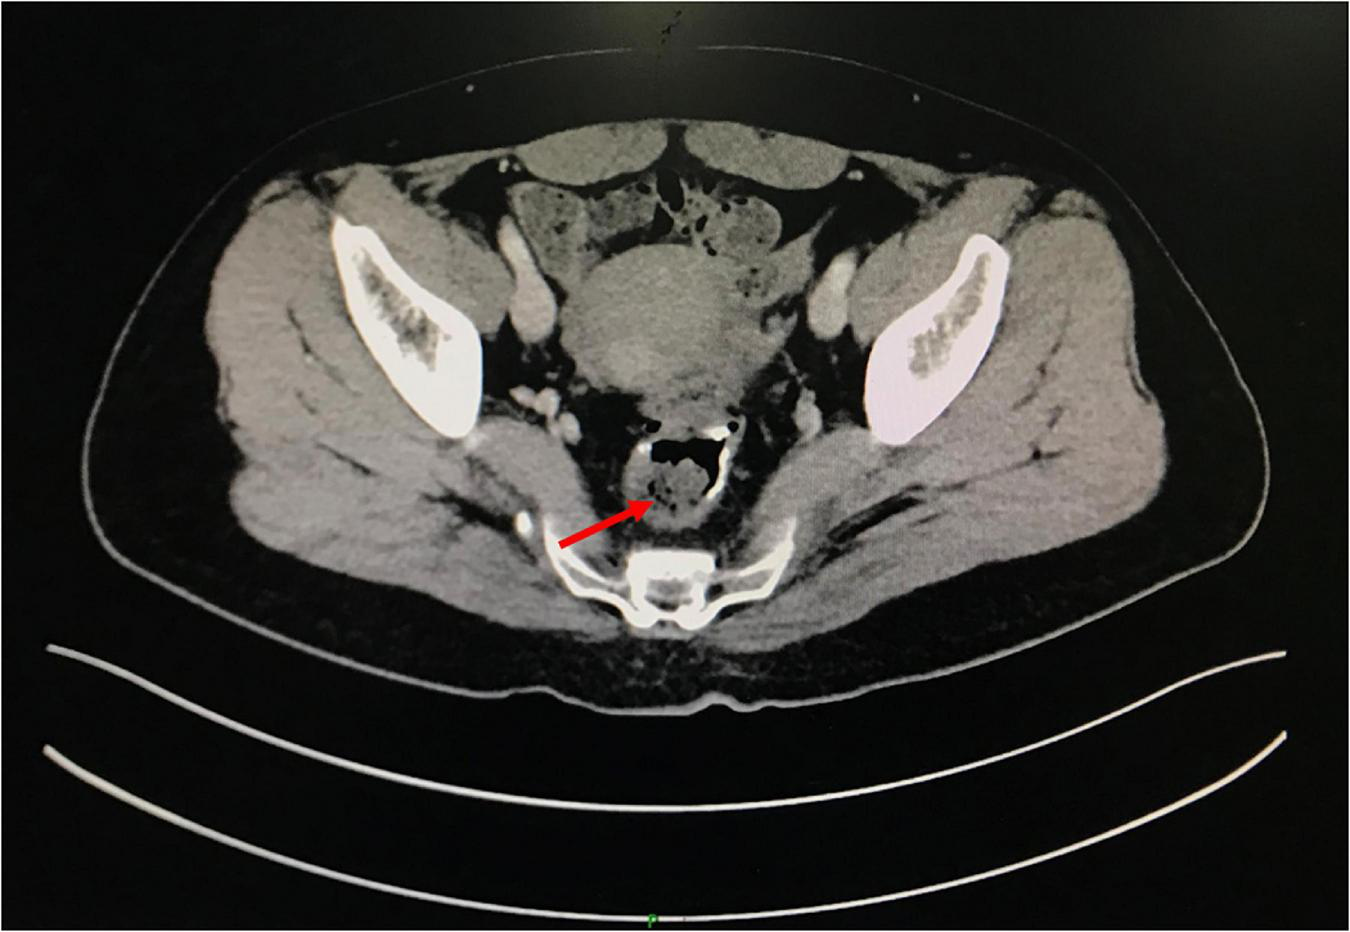

A 49-year-old woman complained of recurrent subumbilical pain without obvious inducement for half a year, and no discomfort such as bloody stool, diarrhea or constipation. The patient underwent radical resection for rectal cancer 14 years ago. The results of physical examination showed mild tenderness in the subumbilical abdomen without rebound pain. There were no significant abnormalities in routine blood parameters and related inflammatory indicators. Colonoscopy showed anastomotic diverticulum combined with stercorolith incarceration (Figure 1A). CT image of the pelvic cavity showed a mass of low density adjacent to the anastomosis (Figure 2). When the local inflammation was relieved by conservative treatment, the patient underwent endoscopic mucosal incision and lithotomy (Figures 1B,C). And the diverticulum was closed with titanium clips (Figure 1D). After 1 year of follow-up, the patient said that the abdominal pain was completely relieved, and the reexamination of colonoscopy showed that the wound healed well (Figure 3).

FIGURE 2

www.frontiersin.org

Figure 2. The pelvic cavity CT image.